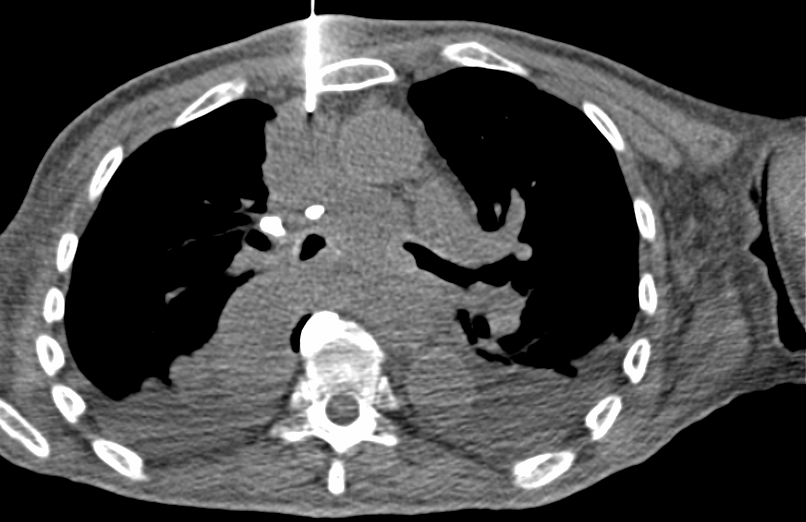

Biopsia de mediastino anterior